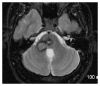

We describe common and less common diseases that can cause magnetic resonance signal abnormalities of middle cerebellar peduncles (MCP), offering a systematic approach correlating imaging findings with clinical clues and pathologic mechanisms. Myelin abnormalities, different types of edema or neurodegenerative processes, can cause areas of abnormal T2 signal, variable enhancement, and patterns of diffusivity of MCP. Pathologies such as demyelinating disorders or certain neurodegenerative entities (e.g., multiple system atrophy or fragile X-associated tremor-ataxia syndrome) appear to have predilection for MCP. Careful evaluation of concomitant imaging findings in the brain or brainstem; and focused correlation with key clinical findings such as immunosuppression for progressive multifocal leukoencephalopahty; hypertension, post-transplant status or high dose chemotherapy for posterior reversible encephalopathy; electrolyte disorders for myelinolysis or suspected toxic-drug related encephalopathy; would yield an appropriate and accurate differential diagnosis in the majority of cases.